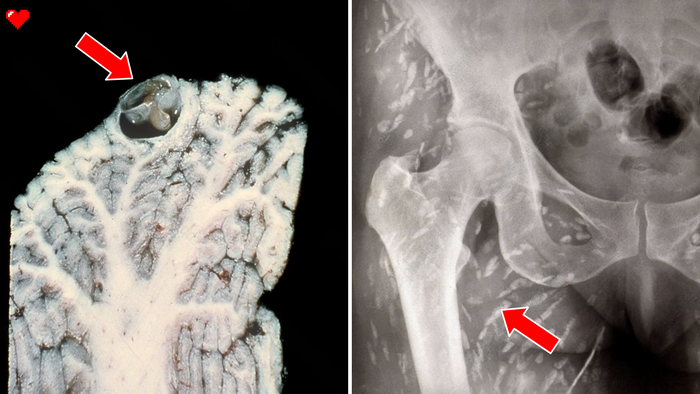

Сколекс свиного цепня. Хорошо видно присоски и крючки, которые предназначены для прикрепления и удержания на стенках кишечника.

Поражение организма, после попадания в организм яиц свиного солитёра. 1 - финны в головном мозге. 2 - финны в тканях.